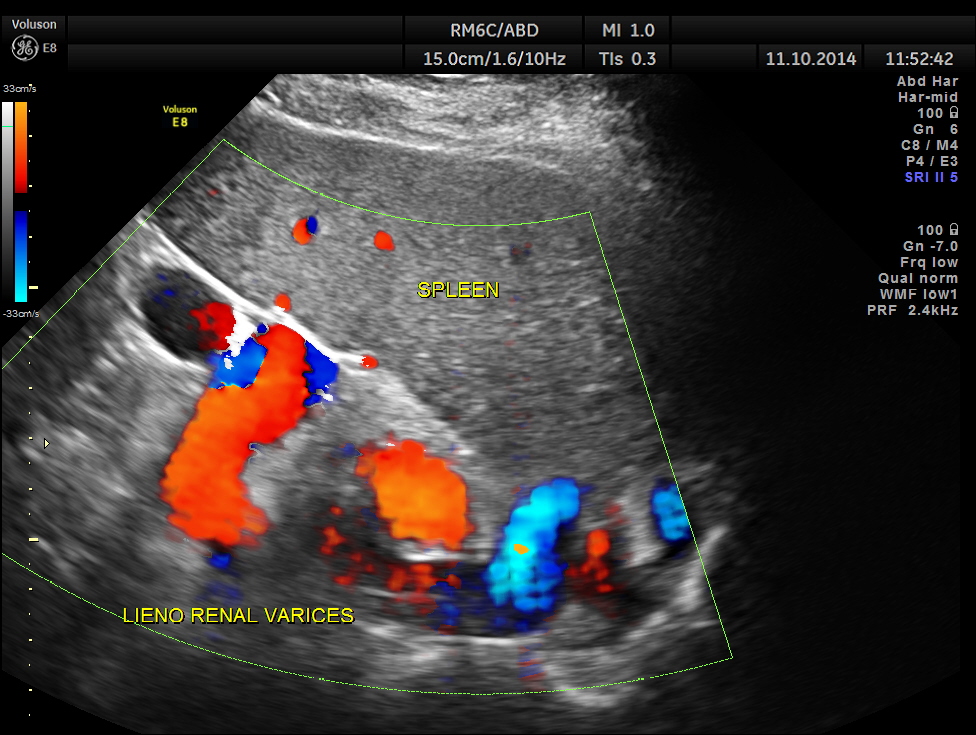

Colour flow imaging of the same.

Variceal dilatation of vessels in the lieno renal ligament. Splenomegaly is also seen.

Ultrasonically a diagnosis of Portal fibrosis with portal hypertension – splenomegaly and lieno renal varices was given.